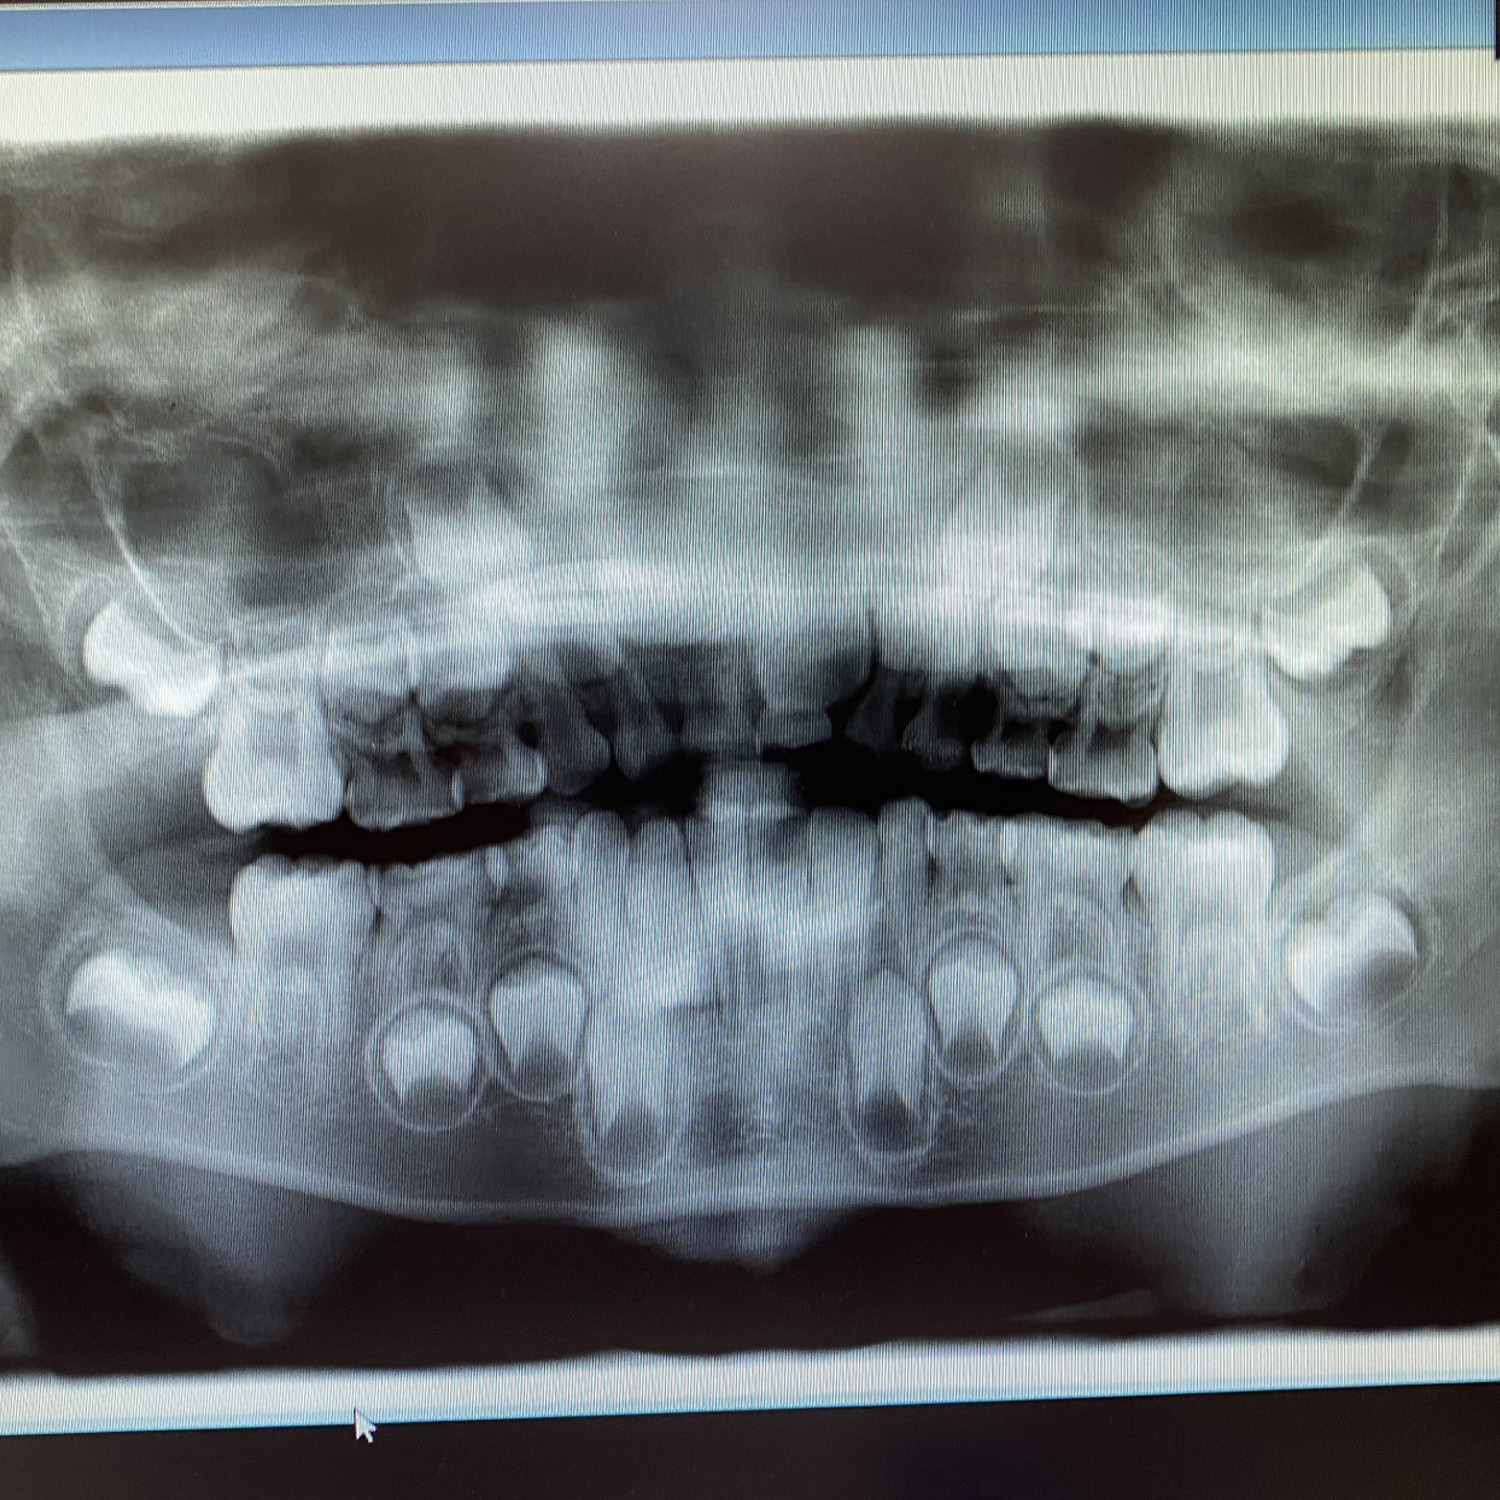

3レントゲン撮影

必要に応じてお口全体の写真(パノラマ写真)もしくは 部分的な写真(デンタル写真)をお撮りします